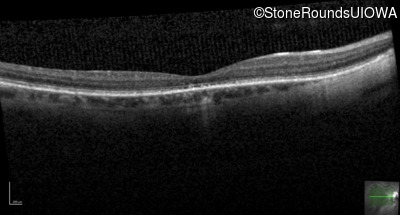

Optical Coherence Tomography - Right - 20/40

Exemplar / OCT Stack

OCT Stack